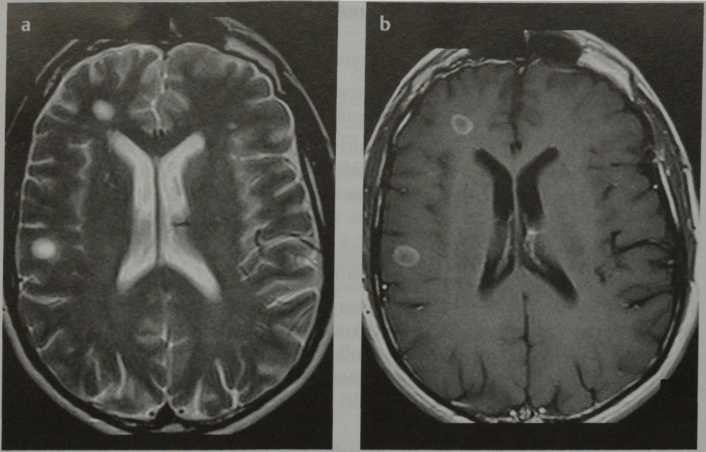

Информация о диссеминированном рассеянном энцефаломиелите